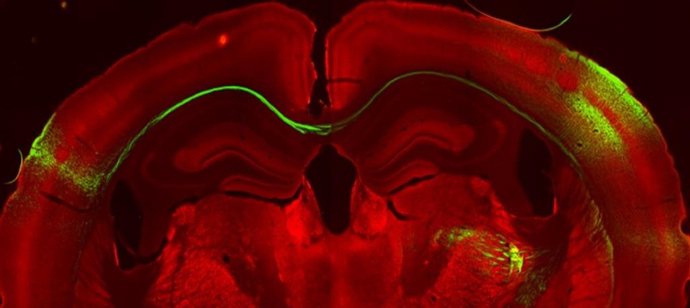

Neurones d'un hemisferi de l'escora somatosensorial primria projecten cap a l'altre hemisferi.

IN-CSIC-UMH.

Fins ara s'havia observat la presncia d'aquests axons, per els investigadors de l'IN han demostrat en ratolins les propietats funcionals d'aquells axons que creuen i fan sinapsi amb l'altre hemisferi. Aquests connecten especialment informació tctil de les parts de la línia mitjana i generen una representació o activació idntica de la informació a banda i banda, permetent processar la informació sensorial de manera contínua.

En aquest treball, el primer autor del qual és Roberto Montanari, han aconseguit descriure de forma precisa el circuit complet que comunica ambdós hemisferis cerebrals: la informació percebuda davant un estímul sensorial viatja a través del cos callós i és processada específicament en una regió molt concreta de la escora somatosensorial primria, al ratolí els barrils de la fila A (RowA). Per tant, aquests representen un centre sensorial per a la comunicació interhemisfrica.

Els investigadors han comprovat que la comunicació entre hemisferis es produeix a la fila A: "És el que s'anomena projecció heterotpica. Per exemple, els barrils de la fila E amb prou feines projecten la fila E de l'altre hemisferi, sinó que ho fan a través de la fila A", explica el director del laboratori de Processament sensoriomotriu en rees subcorticals de l'IN Ramón Reig, i afegeix que aix és molt interessant perqu és precisament a la fila A on es troben els receptors dels bigotis de la línia mitjana.